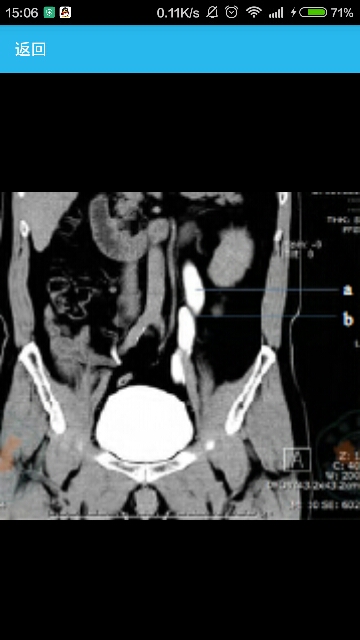

辅助检查超声:左重复肾畸形,左上半肾扩张,左输尿管开口囊肿;逆行肾盂造影:左侧上肾盂肾盏扩张积水明显,肾盏杯口消失,左输尿管下端扩张积水;CT:左重复肾双输尿管,左上半肾积水(如图);MRI:左重复肾伴左上半肾重度积水,引流左上半肾的输尿管中下段明显扩张。